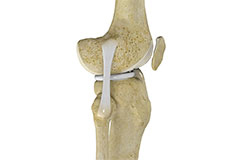

High Tibial Osteotomy